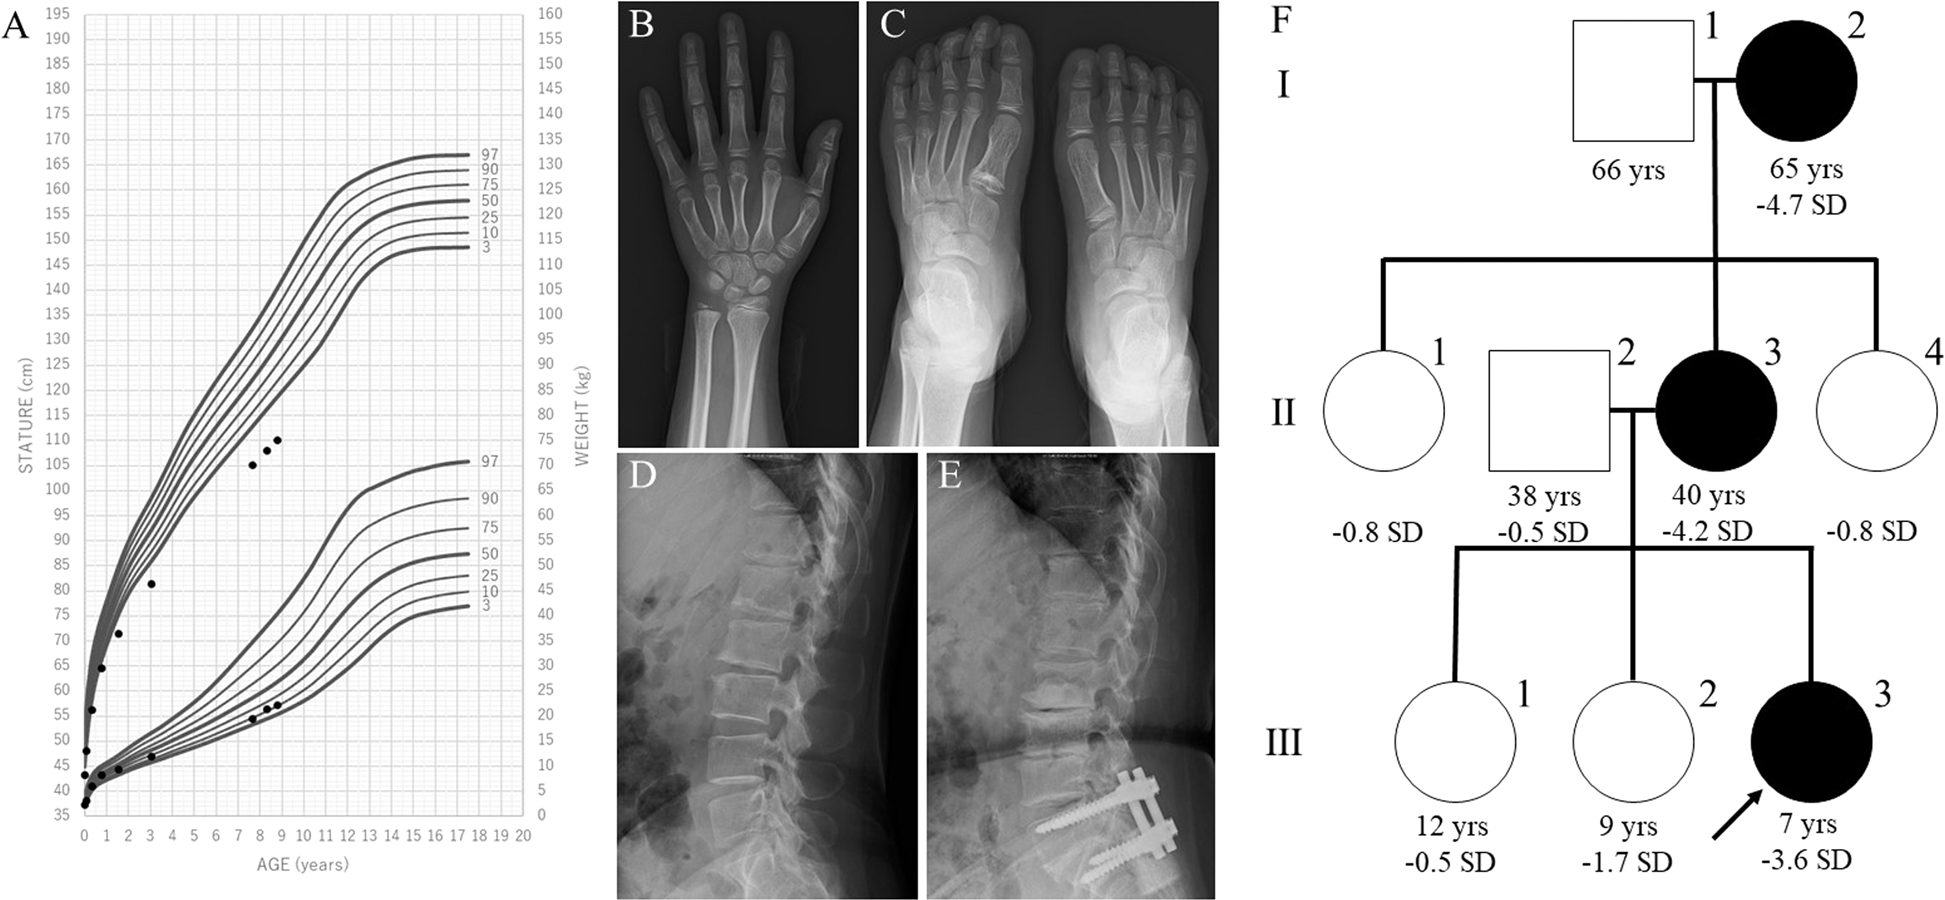

Fig. 1: Clinical information of the family members.

A Growth chart of the proband. Heights and weights are shown as black points. B X-ray of the proband’s left hand. Mild shortening of the 4th and 5th metacarpals and shortening of the 1st distal phalanx are shown. The bone age was interpreted as 8 years and 10 months using the Greulich and Pyle method. C X-ray of the proband’s feet. Cone-shaped epiphyses of the left 1st and 4th metatarsals and large epiphyses of the 5th distal phalanges are shown. D, E Lumbar spine X-rays of the proband’s mother and maternal grandmother. Narrowed intervertebral spaces and endplate irregularities are shown. F Pedigree of the studied family. The arrow indicates the proband (III-3). The family members with short stature carrying ACAN mutations are indicated with filled symbols. Ages and heights in standard division score are reported below each symbol.